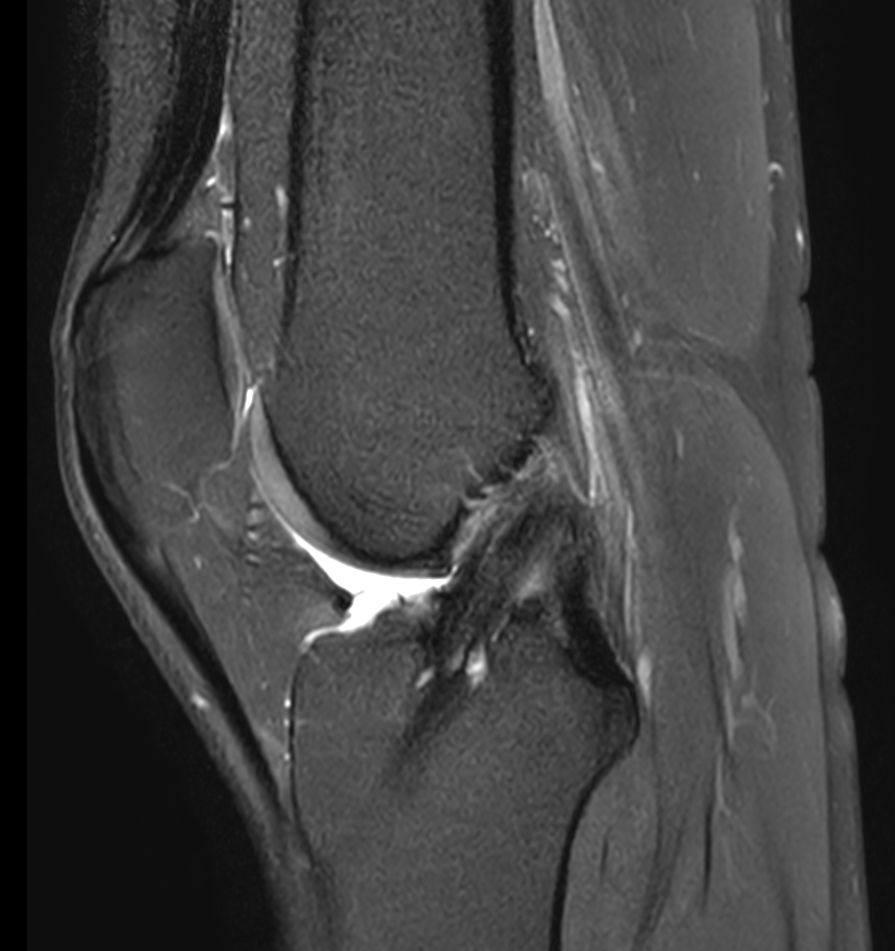

Sagittal PDw SPAIRCompressed SENSE